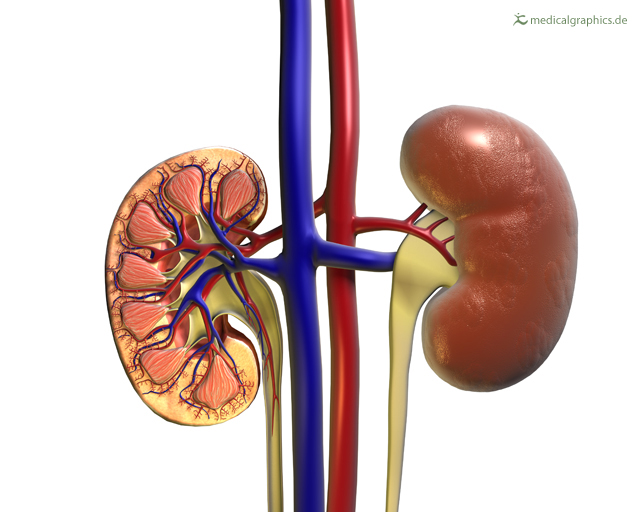

Строение почек человека: Фото и описание